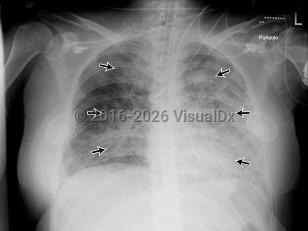

Acute respiratory distress syndromeAcute respiratory distress syndrome

Pulmonary edema

Acute eosinophilic pneumoniaAcute eosinophilic pneumonia